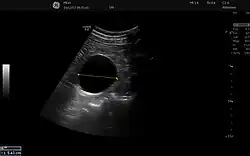

Obstetricia

Esta técnica diagnóstica también se conoce como ecografía o sonografía.[16]

La máquina de ultrasonido tiene cristales piezoeléctricos que al ser estimulados por electricidad vibran produciendo ondas sonoras de alta frecuencia que hacen eco en las estructuras corporales retornando a los cristales que nuevamente estimulados ahora por ultrasonido producen pequeños voltajes que son procesados de acuerdo a su intensidad y tiempo de retorno mediante un computador que tiene un convertidor de barrido digital creando así las imágenes. A diferencia de los rayos X, en este examen no se presenta ninguna exposición a la radiación ionizante y no se ha detectado ningún riesgo utilizado con los aparatos apropiados para diagnóstico. En la actualidad existen ecógrafos del tamaño de un celular que pueden ser empleados para diagnóstico inmediato.[17]

Las frecuencias típicas utilizadas para aplicaciones en abdomen pueden ir desde 2,0 MHz a 5,0 MHz mientras que para regiones como mama, músculo-esqueléticas, tiroides, etc., las frecuencias pueden oscilar entre 8,0 MHz a 16,0 MHz. Se utilizan frecuencias más altas para medición de estructuras muy pequeñas y superficiales